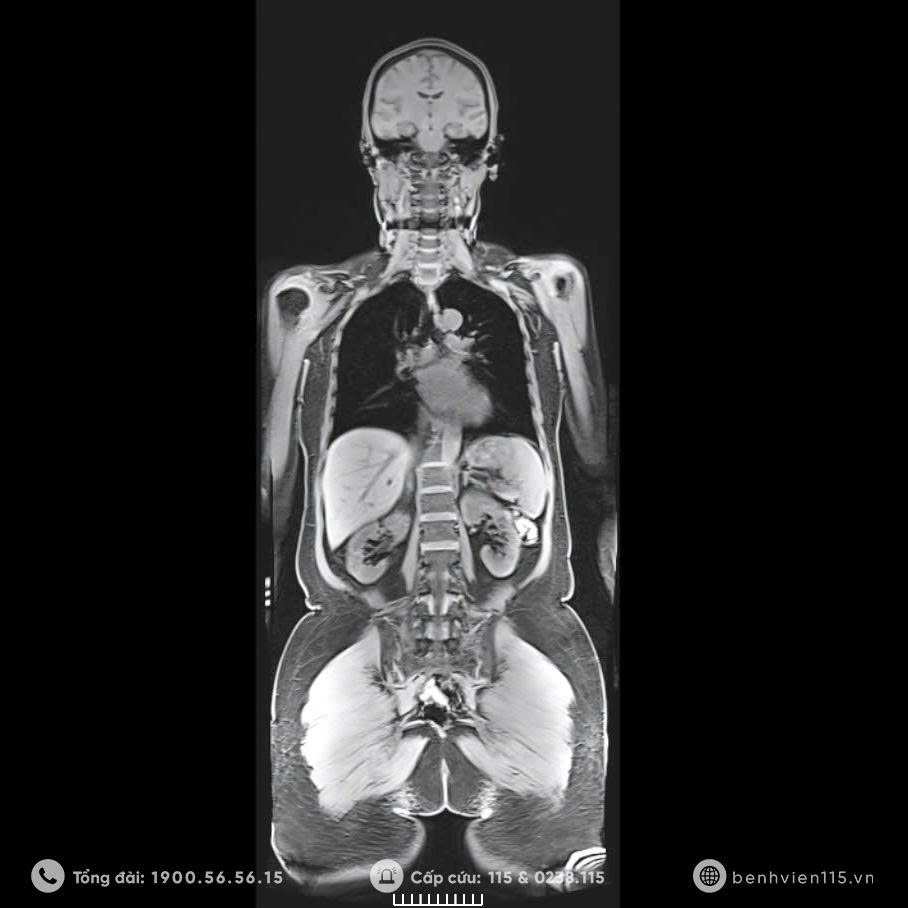

Hình ảnh cộng hường từ toàn thân trên máy MRI 3.0 Tesla

Một trong những phương pháp được sử dụng để tầm soát các bệnh lý tiềm ẩn chính là chụp Cộng hưởng từ (MRI) – Công cụ phát hiện sớm, nhanh chóng và chính xác. Ngày nay, MRI được coi là “tiêu chuẩn vàng” trong chẩn đoán hình ảnh các bệnh lý não, tủy sống và cột sống,…

MRI sử dụng từ trường và sóng radio để cung cấp hình ảnh chi tiết và chính xác về cơ thể. Chỉ mất khoảng 10 phút, hệ thống có thể ghi lại hình ảnh chi tiết bên trong cơ thể mà các phương pháp chụp X-quang hay CT scan thông thường khó phát hiện.

Nhờ đó, chúng tôi đáp ứng được nhu cầu phát hiện những bệnh lí chuyên sâu về đột quỵ, chấn thương,… Đặc biệt tầm soát khối u toàn cơ thể trong vấn đề phát hiện sớm bệnh ung thư, đánh giá những tổn thương di căn. Giúp phát hiện sớm nguyên nhân ẩn sâu như thoát vị đĩa đệm, thoái hóa cột sống, chèn ép rễ thần kinh, tai biến mạch máu não, khối u,…